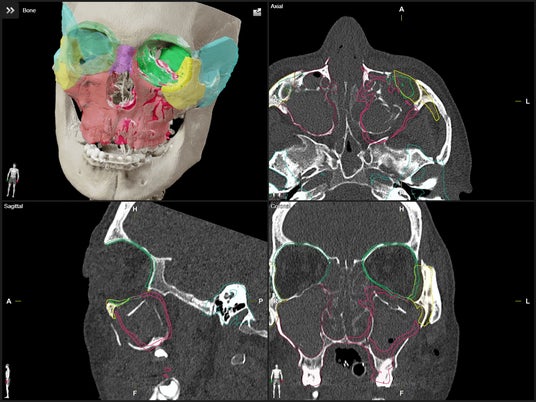

手術計画ソフトウェア「Elements」 - ミラーリング機能

「Elements」には、患者様ごとにターゲット構造やリスク部位を高精度で自動描出する機能が搭載されており、より正確な手術のシミュレーションと個別最適化された手術計画の立案が可能です。また、「Kick(R) 2」による術中ナビゲーション支援により、リアルタイムで解剖構造を確認しながら手術を進めることができ、手術の精度向上と安全性の確保に大きく貢献します。